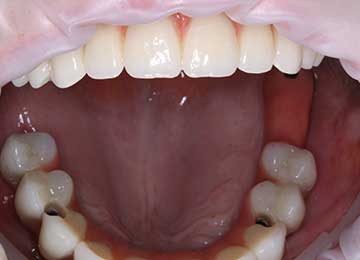

Имплантация зубов: фото «До» и «После»

Фото ДО

Фото ПОСЛЕ

Наведите для просмотра

All-on-4